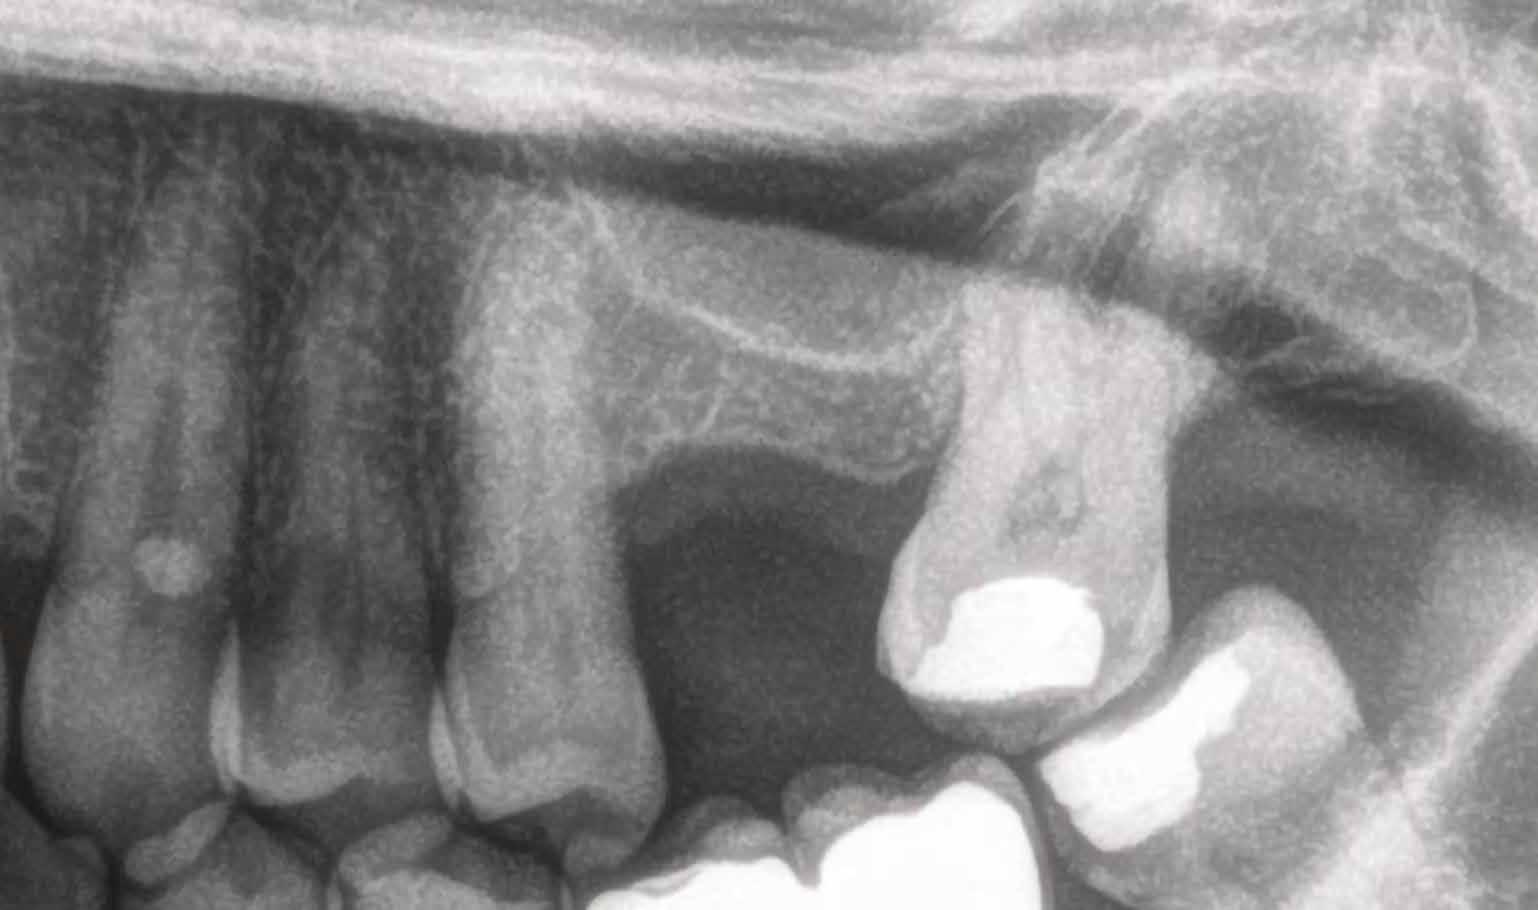

A CT metszetekben a 48-as gyökerei körbeölelik a canalis mandibularist, amelyet piros nyíllal jelöltünk a fotókon.

Szeretnék mutatni néhány ábrát az egyik bonyolult esetről, a közelmúltból. A CT-n látszik, hogy a három gyökér teljesen „körbenőtte” az ideget. Van olyan frontális metszeti kép, ahol csak a gyökerek vannak a nervus körül, ezen a szakaszon egyáltalán nincs meg a csontos fala a canalisnak. Szeparációs technikával, viszonylag könnyen, minimális traumával, szövődménymentesen sikerült eltávolítani a fog minden részét. A várakozásnak megfelelően, a beteg nem számolt be paraesthesiáról.